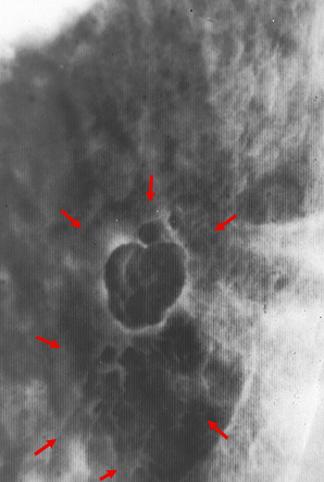

Criteria of Hist.ClassificationMalignant epithelial tumor/Adenocarcinoma

LocationStomach/Body

Technique, MethodX-ray

Macroscopic TypesType 0/IIa (IIa+IIb) Superficial elevated and flat type

Size35 - 40

Depth of Tumor Invasionmucosa